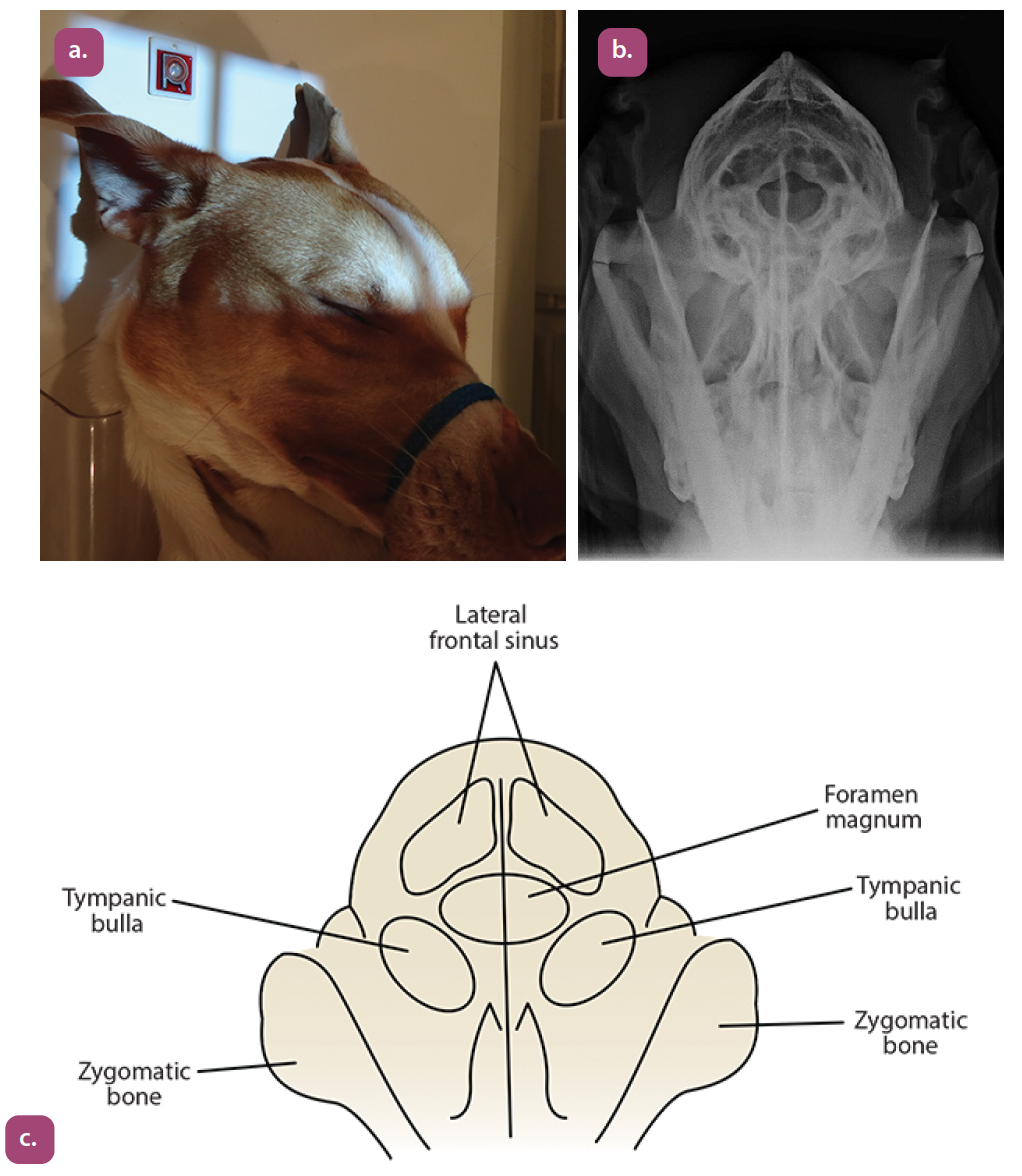

rostrocaudal foramen magnum projection